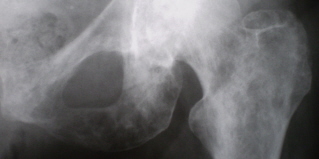

Иллюстрация 2 – определяются множественные очаги деструкции костной ткани, хорошо дифференцирующиеся в области седалищной кости и её ветви, в области шейки, проксимального мета – диафиза левой бедренной кости.

Иллюстрация 3 – множественные очаги деструкции округлой формы, как бы «выбитые из кости острым пробойником» определяются в области седалищного бугра, ветвях седалищной и лонной костей, с локальной «нечеткостью» кортикального слоя ветви лонной кости по нижнему контуру.